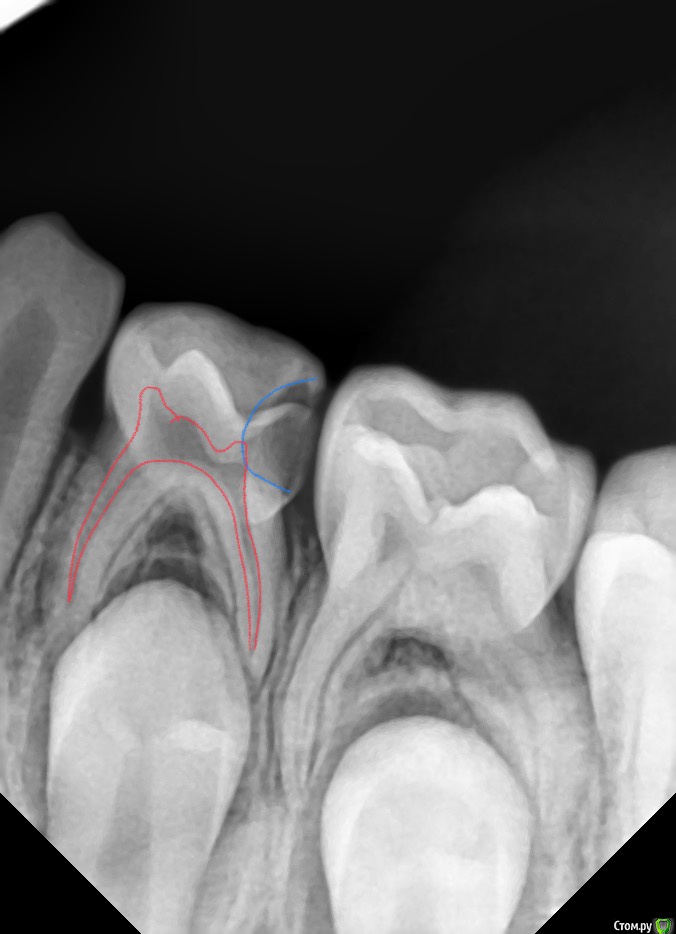

CRAZYDUCK Опубликовано 30 мая, 2018 Автор Поделиться Опубликовано 30 мая, 2018 Про обратимый пульпит .( ампутацию) Лечение методом витальной АМПУТАЦИИ. Даше в июле 6 лет . Познакомились мы полтора года назад , но сотрудничать не получилось , направлены для лечения в условиях общего обезболивания ( наркоз ) к ☺ @toothfairymila После лечения в условиях наркоза дети легче идут на контакт . Ребёнка не узнать - если до лечения в наркозе Даша даже в кресло садилась со слезами , то после - милые подарки , осторожно , но готова сотрудничать . Даша внимательно смотрит на моих ассистентов , взгляд изучающий ( можно этому человеку доверять или нет ). Маме Даши огромное спасибо - очень ответственно относится к регулярным осмотрам . Выявили скрытые кариозные полости и Даша доверилась лечиться в обычных условиях ( без наркоза ). 6.4 - обратимый пульпит , изначально было обширное разрушение , восстановлено пломбой в наркозе , поэтому лепить там пломбу ещё больше нет смысла. После ампутации -спонтанный гемостаз ( сравните с предыдущим случаем). Промываем ХГ 2% , мта на устья , IRM , коронка. 6.5 - обширная реставрация окклюзионно и начался кариес на медиальной контактной поверхности . Зуб должен меняться примерно в 10 лет ( 9-11 лет средний срок), то есть хочется , чтобы он постоял ещё года четыре , поэтому покрываем коронкой . Ждём Дашу на осмотр через 3-4 месяца.П.С. На заметку молодым коллегам - На снимке обвела зелёным нерентгенконтрастную реставрацию на зубе 6.3 , похоже на кариес , но это очень хорошая реставрация ! 1 Ссылка на комментарий

CRAZYDUCK Опубликовано 31 мая, 2018 Автор Поделиться Опубликовано 31 мая, 2018 Док, такая эндодонтия приемлема? Все условия соблюдены, коффердам, гипохлорит, ничего не кровило. смущают медиальные каналы - один кажется совсем мало запломбирован , а второй не так плотно , как дистальный ? Скорее всего , что все будет хорошо . Паста может рассосаться в медиальных быстрее , чем в дистальном, но если патологических изменений ( разрежения) не будет , то это норма . Каналы могут быть пустыми до смены . Сделайте снимки каждые 3-4 месяца в течение года . Я поняла , что хорошо заполняются пастой сухие каналы . Тонкой насадкой на пылесосе и бумажными пинами сушу. Ссылка на комментарий